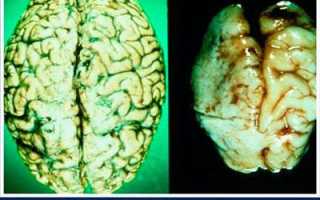

Таким образом, в научном мире известно, что сто граммов водки убивает порядка 8000 нейронов, которые обеспечивают этот орган нервными импульсами для мыслительного процесса. Такие поражения не проходят бесследно – «шрамы», возникающие на месте массового повреждения, приводят к сморщиванию и буквально высушиванию мозга и, следовательно, уменьшению его объема и массы.

Деградация личности, появляющаяся от подобного воздействия, неизбежна. Она выражается в потере адекватности, снижении интеллекта, ухудшении памяти, внимания, сообразительности. Отмирание целых центров, отвечающих за моральный облик, приводит к потере нравственности, общей деградации, утрате чувства стыда и способности к самокритичности. В этом состоянии человек начинает производить неадекватные, асоциальные поступки, в которых часто не несет отчета. Нарушенная затылочная часть мозга, которая также поражается очень быстро, приводит к нарушениям походки, сбою в координации и двигательной функции в целом. Поражение сосудов головного мозга приводят к изменениям в психике, которые со временем начинают выражено прогрессировать.

Пагубное влияние алкоголя на здоровье подтверждается многочисленными научными опытами, данными патологоанатомов и прочими документами, наглядно показывающими степень поражения органов от употребления этого продукта.